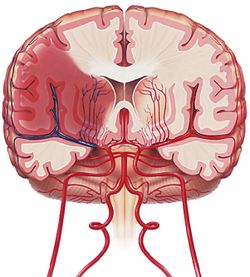

النزف تحت العنكبوتية «أم الدم هي توسع غير طبيعي في جدار أحد الشرايين. يؤدي تمزق أم الدم عادة إلى خروج الدم بغزارة على الفراغ المحيط بالدماغ».

2ـ النزيف تحت العنكبوتية subarachnoid hemorrhage: يقدر بنحو 5% من الأمراض الوعائية الدماغية. وفيه يحدث نزيف حول التلافيف الدماغية (وخاصة تحت الطبقة السحائية المغطية لسطح الدماغ المعروفة باسم العنكبوتية).

ـ عوامل الخطورة والأسباب: من أهم الأسباب المؤدية لهذا النوع من النزيف رضوض الدماغ والتشوهات الوعائية الدماغية (ولاسيما أمهات الدم والتشوهات الشريانية الوريدية) ومن عوامل الخطورة أيضاً فرط الضغط الشرياني والتدخين.